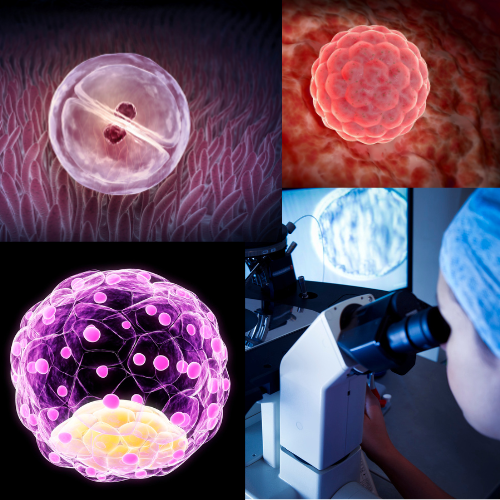

Skôr ako niečo vidíme

Zmena vzniká ešte skôr ako sme ju chopný postrehnúť ultrazvukom. Od 6-7 týždňa podľa kvality ultrazvuku už zaznamenávame srdcovú aktivitu plodu a drobné pohyby plodu.